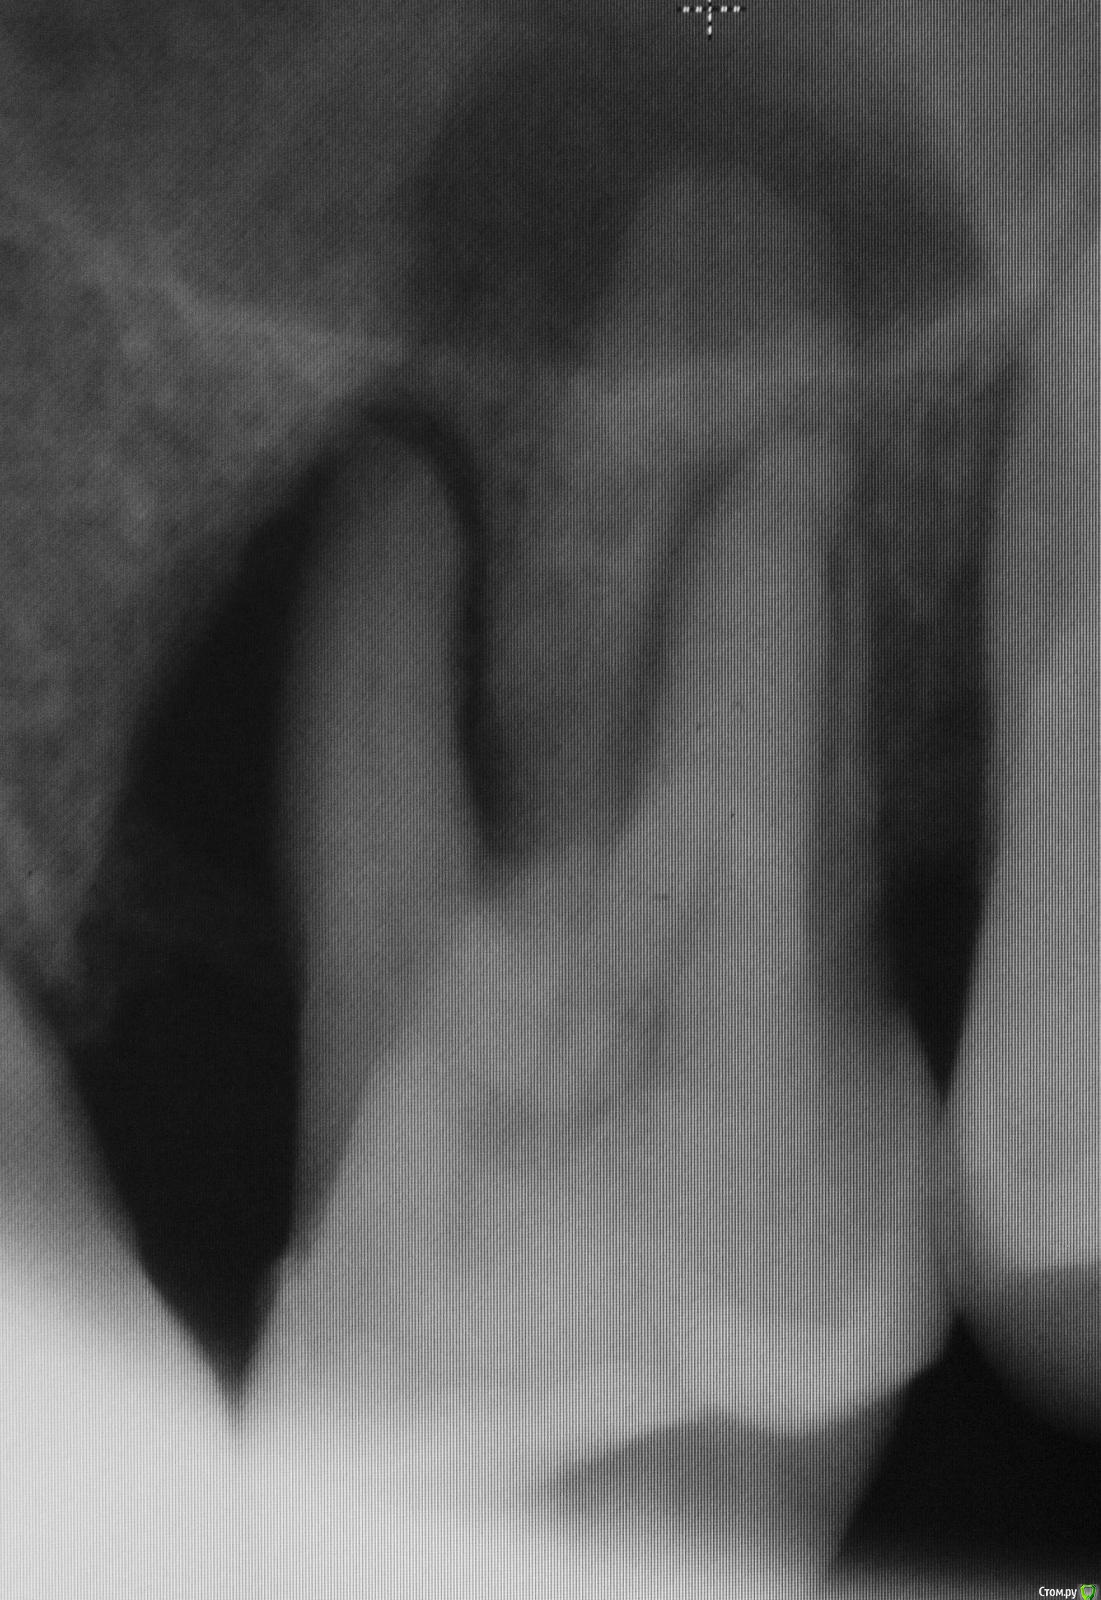

DmitrySH Опубликовано 28 июля, 2015 Поделиться Опубликовано 28 июля, 2015 (изменено) Такой вот сюрприз от знакомого, у которого на весь рот пара пломб да одна коронка. С гигиеной только плохо, как я с ним не боролся. Не могу понять этиологию. http://s008.radikal.ru/i303/1507/f8/dcbbdfee70a4.jpg Изменено 28 июля, 2015 пользователем dmitrySH Ссылка на комментарий

АнтонТЛТ Опубликовано 28 июля, 2015 Поделиться Опубликовано 28 июля, 2015 Да там как-будто кариозная полость сообщается с пульпарной камерой Ссылка на комментарий

diesel87 Опубликовано 28 июля, 2015 Поделиться Опубликовано 28 июля, 2015 Да там как-будто кариозная полость сообщается с пульпарной камеройХочешь сказать тупо прохлопанный периодонтит?) Ссылка на комментарий

diesel87 Опубликовано 28 июля, 2015 Поделиться Опубликовано 28 июля, 2015 Ну по данным срезам похоже, как на самом деле хз))И от него еще и гайморит?) Ссылка на комментарий

DmitrySH Опубликовано 28 июля, 2015 Автор Поделиться Опубликовано 28 июля, 2015 Визуально кариеса нет. Пациент из той группы, у которой зубы могут быть покрыты кучей налета, все желтого цвета, но кариесу мало подвержены.КТ делал, хотел понять что с костью вокруг зуба, что с пазухой. Небно абсцесс, все мягкое, отечное. Изначально думал, что только пародонтальная проблема. С гайморитом отдельно надо разбираться, с другой стороны в пазухе вообще просвета нет. Ссылка на комментарий

DmitrySH Опубликовано 29 июля, 2015 Автор Поделиться Опубликовано 29 июля, 2015 (изменено) Небно зондируется до апекса, на холод не реагирует, впрочем и перкуссия тоже отрицательна. Болит только слизистая небно. Сейчас пообщался, после вчерашней ревизии "кармана" все прошло, ничего не болит. Он в субботу еще в отпуск собрался Изменено 29 июля, 2015 пользователем dmitrySH Ссылка на комментарий